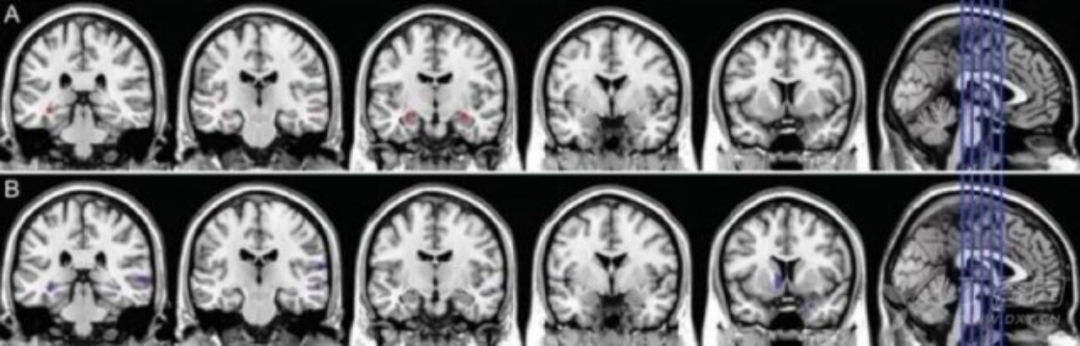

3.结构磁共振(sMRI) sMRI 可测量区域性或全脑体积大小,反映因细胞损伤、轴突退变、突触失调引起的结构萎缩。最早出现并进行性加重的内侧颞叶结构萎缩可能是 AD 早期出现的特征性改变,其中海马萎缩,被认为是 MCI 进展到 AD 痴呆的最佳标志物。研究还发现,AD 早期人群的皮层灰质、内嗅皮层和海马旁回也存在萎缩。MCI 患者可出现皮质厚度变薄和全脑体积变小,可用于预测 MCI 向 AD 的转化。2011 年 NIA-AA 诊断标准将 sMRI 作为 AD 神经损伤标记物之一;然而 2014 年最新的 IWG-2 标准认为 sMRI 可能更适合用于测量和监测疾病过程。

4 正常对照组(CN)、aMCI 和 AD 患者的海马体积结构 MRI 成像